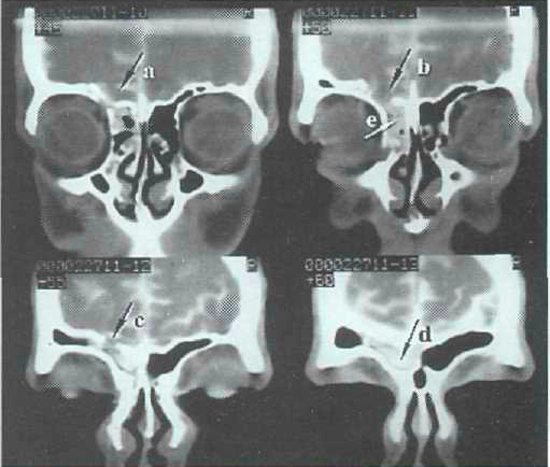

В настоящее время наиболее информативными являются инструментальные методы диагностики перелома носа. Например, такие как:

- компьютерная томография;

Компьютерная томография дает более точную информацию и линиях перелома носа, возможном смещении костных носовых отломков.

При этом можно выявить повреждения глазниц, носовых пазух и костей черепа.